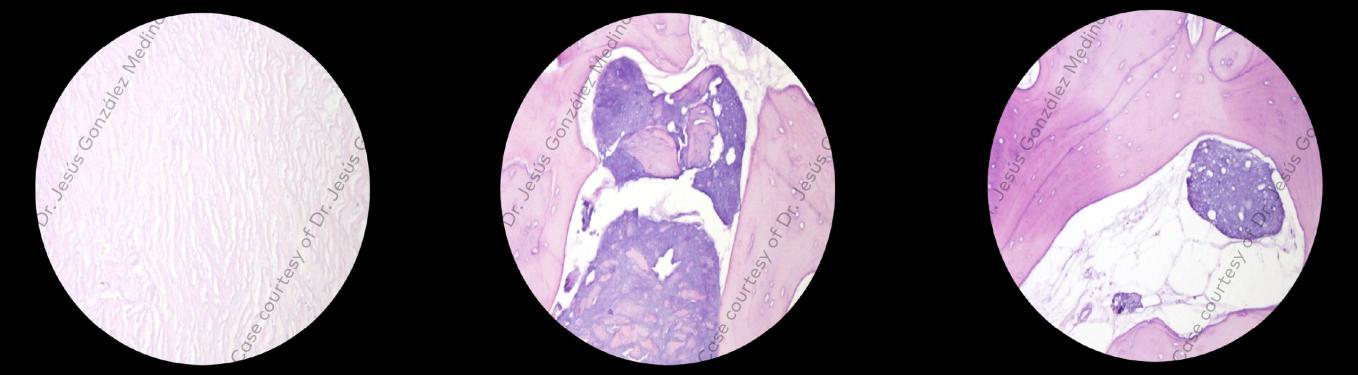

Clinical situation: Missing 24-25, and 26 exhibits grade III mobility, indicating severe bone loss vertically 11 mm at the deepest area and horizontally 2 mm, and chronic periodontitis.

Surgical solution: Extraction of 26 and vertical bone augmentation using creos syntoprotect Ti-reinforced PTFE membrane and 50% xenograft and 50% autologous bone to attain the necessary bone height for implant placement of NobelActive® TiUltra™ implants.